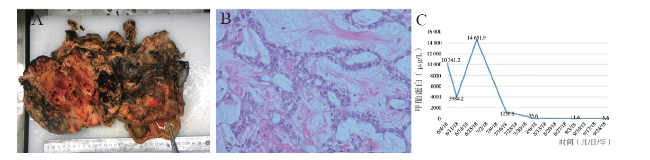

血常规示血红蛋白74 g/L,红细胞2.97×1012/L,白细胞7.82×109/L,中性粒细胞0.722,淋巴细胞0.202,血小板计数306×109/L。血清癌抗原125(CA125)74.1 kU/L,人附睾蛋白4 30.1 pmol/L,血清甲胎蛋白10 341.2 μg/L,癌胚抗原(CEA)0.3 μg/L,血清人绒毛膜促性腺激素(HCG)5 U/L。彩色多普勒超声(彩超)检查提示盆腹腔内见巨大稍高回声团,上达脐水平,两侧达髂窝,边界清,包膜光滑,内回声不均,可见数个小暗区。彩色多普勒血流显像(CDFI):稍高回声团内可见较丰富血流信号,引出低阻动脉血流频谱,右侧卵巢显示不清,盆腔巨大实性包块,考虑右侧卵巢恶性肿瘤可能性大(图1)。

图1 一例后腹膜卵黄囊瘤患者入院时的盆腹腔彩超检查